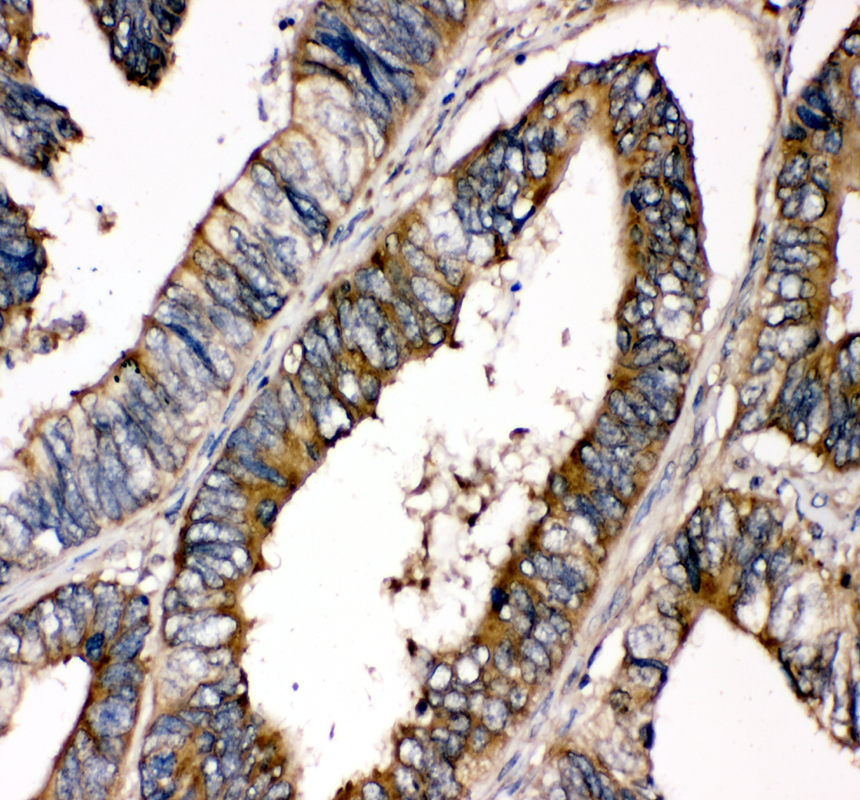

IHC analysis of SHP2/PTPN11 using anti-SHP2/PTPN11 antibody (PB9675).

SHP2/PTPN11 was detected in a paraffin-embedded section of human colon cancer tissue. The tissue section was incubated with rabbit anti-SHP2/PTPN11 Antibody (PB9675) at a dilution of 1:200 and developed using HRP Conjugated Rabbit IgG Super Vision Assay Kit (Catalog # SV0002) with DAB (Catalog # AR1027) as the chromogen.